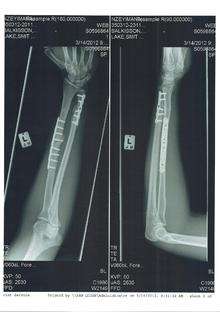

Golden Doodle dog hip xray posterior view